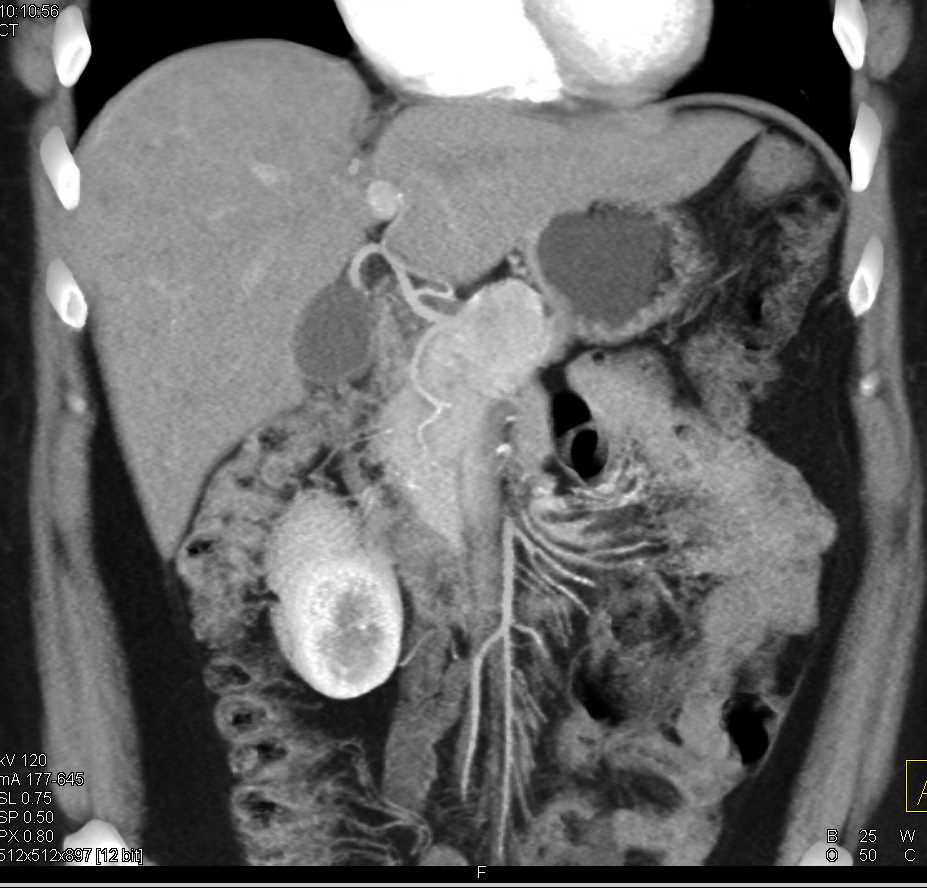

Neuroendocrine Tumor Body of Pancreas